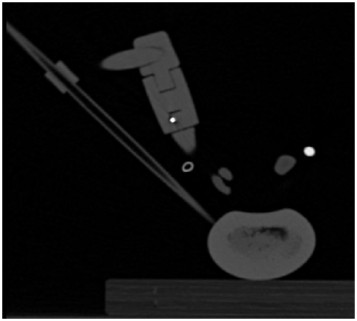

In this project, I iteratively designed (via CAD, 3D Printing and Machining) a Spinal Cavity Creator capable of removing cylindrical-shaped intervertebral disc space material to aid TLIF surgeries for Degenerative Spondylolisthesis. Specifically, this involved conducting a modular design approach as part of 4 distinct teams: 1. Mechanical, responsible for design of the actual mechanical drill bit and shaft interfaced to a pneumatic drill chuck, together with a guide and mount attached to a spinal cross-linker and an arm that would guide a linear stage containing the drill chuck, 2. Image Guidance, responsible for writing scripts to enable determination of the correct trajectory for drilling via image registration using pre-op MRI and real-time CT images, 3. Sensing, responsible for design of appropriate electronic/mechanical sensing equipment that would prevent contact with blood vessels and nerve roots near the foramen, and, 4. Testing, responsible for design of a fully-integrated test-bench for testing each of the aforementioned modules and verifying operation of the fully assembled drill.